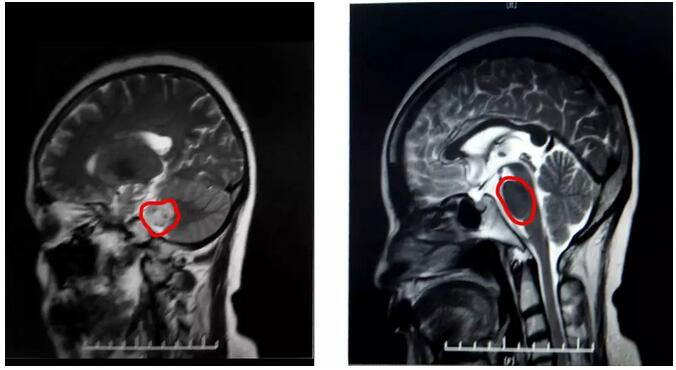

不查不知道,一查嚇一跳!呂阿姨被確診患有右側(cè)聽神經(jīng)瘤。聽神經(jīng)瘤雖然是一種良性腫瘤,但若不進(jìn)行手術(shù)切除,會(huì)像氣球一樣逐漸膨脹,最終壓到周圍的神經(jīng)和血管,導(dǎo)致患者出現(xiàn)耳鳴、聽力下降、突發(fā)性耳聾、共濟(jì)失調(diào)、語言不清和發(fā)音困難等癥狀。病情嚴(yán)重者,甚至可能發(fā)生腦疝,危及生命。

據(jù)磁共振影像顯示,呂阿姨的腫瘤位于內(nèi)聽道與中腦、小腦交界處,還很可能與面神經(jīng)粘連程度嚴(yán)重,而由于腫瘤巨大,聽神經(jīng)、面神經(jīng)大多受壓變得菲薄,術(shù)中辨認(rèn)困難,術(shù)后難以保留功能;同時(shí)術(shù)中處理不當(dāng)還易影響小腦、腦干等功能;這些困難無疑都決定了這將是一臺(tái)較高難度的手術(shù)。

▲ 術(shù)后CT顯示腫瘤基本已被切除